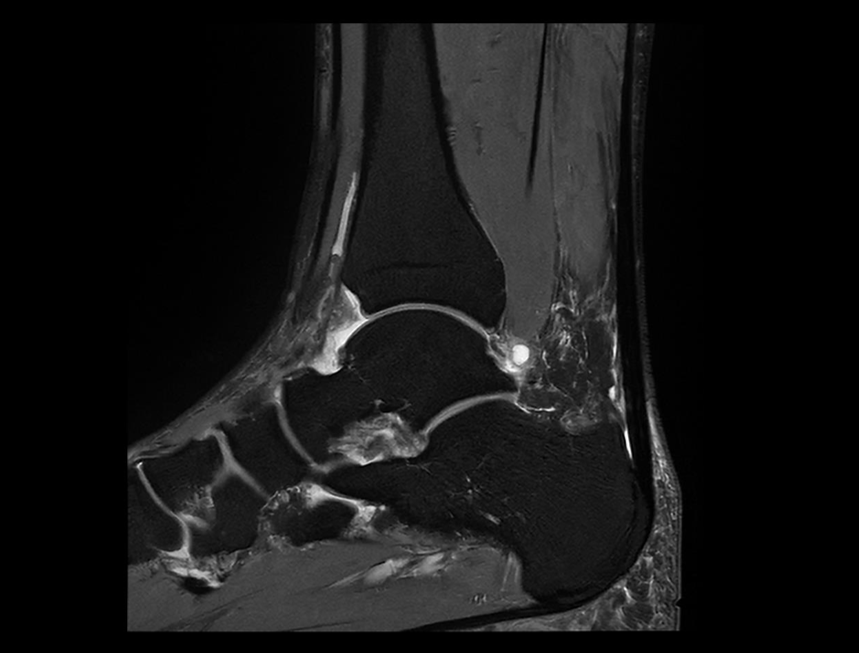

Boundless Clinical Scenarios

작은 해부학적 구조물을 더욱 정확하게 묘사하여 진단 능력을 확장시킵니다.

Technology Required for Ultra-wide Imaging

3.5MW의 최대 출력을 갖춘 차세대 GPA.

45mT/m 및 200 T/m/s의 그라디언트 성능.

0.029ppm @30 DSV 균일성 (일반적인 값).